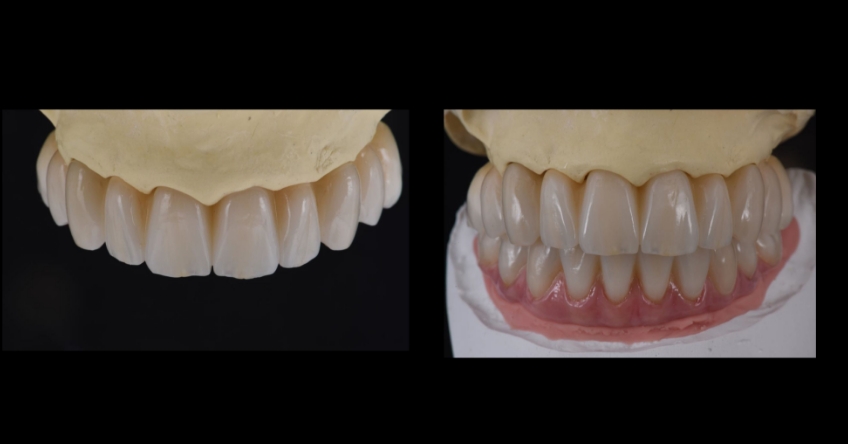

Once the patient understood the nuances between graft vs. a graft-less solution, she opted for a combination of anterior and ZIs instead of grafting the sinuses.

Ultimately, the patient was treated using a combination of traditional and zygomatic implants, allowing her to transition into the definitive prosthesis uneventfully and in a reasonable time frame. This prosthetic design aimed to improve the distribution of occlusal forces and provide enhanced structural support for the final prosthesis.

Comparing zygomatic implants (ZI) vs. bone grating can affect the outcome for your patient. The selection of the proper combination of traditional and ZIs is based on the amount of residual maxillary alveolar bone, the biomechanical requirements of the final dental implant rehabilitation, finances, and surgeon and restorative dentist preferences and experience. The most critical factor for success is the establishment of a prosthetically driven treatment plan between the surgeon and the restorative dentist.